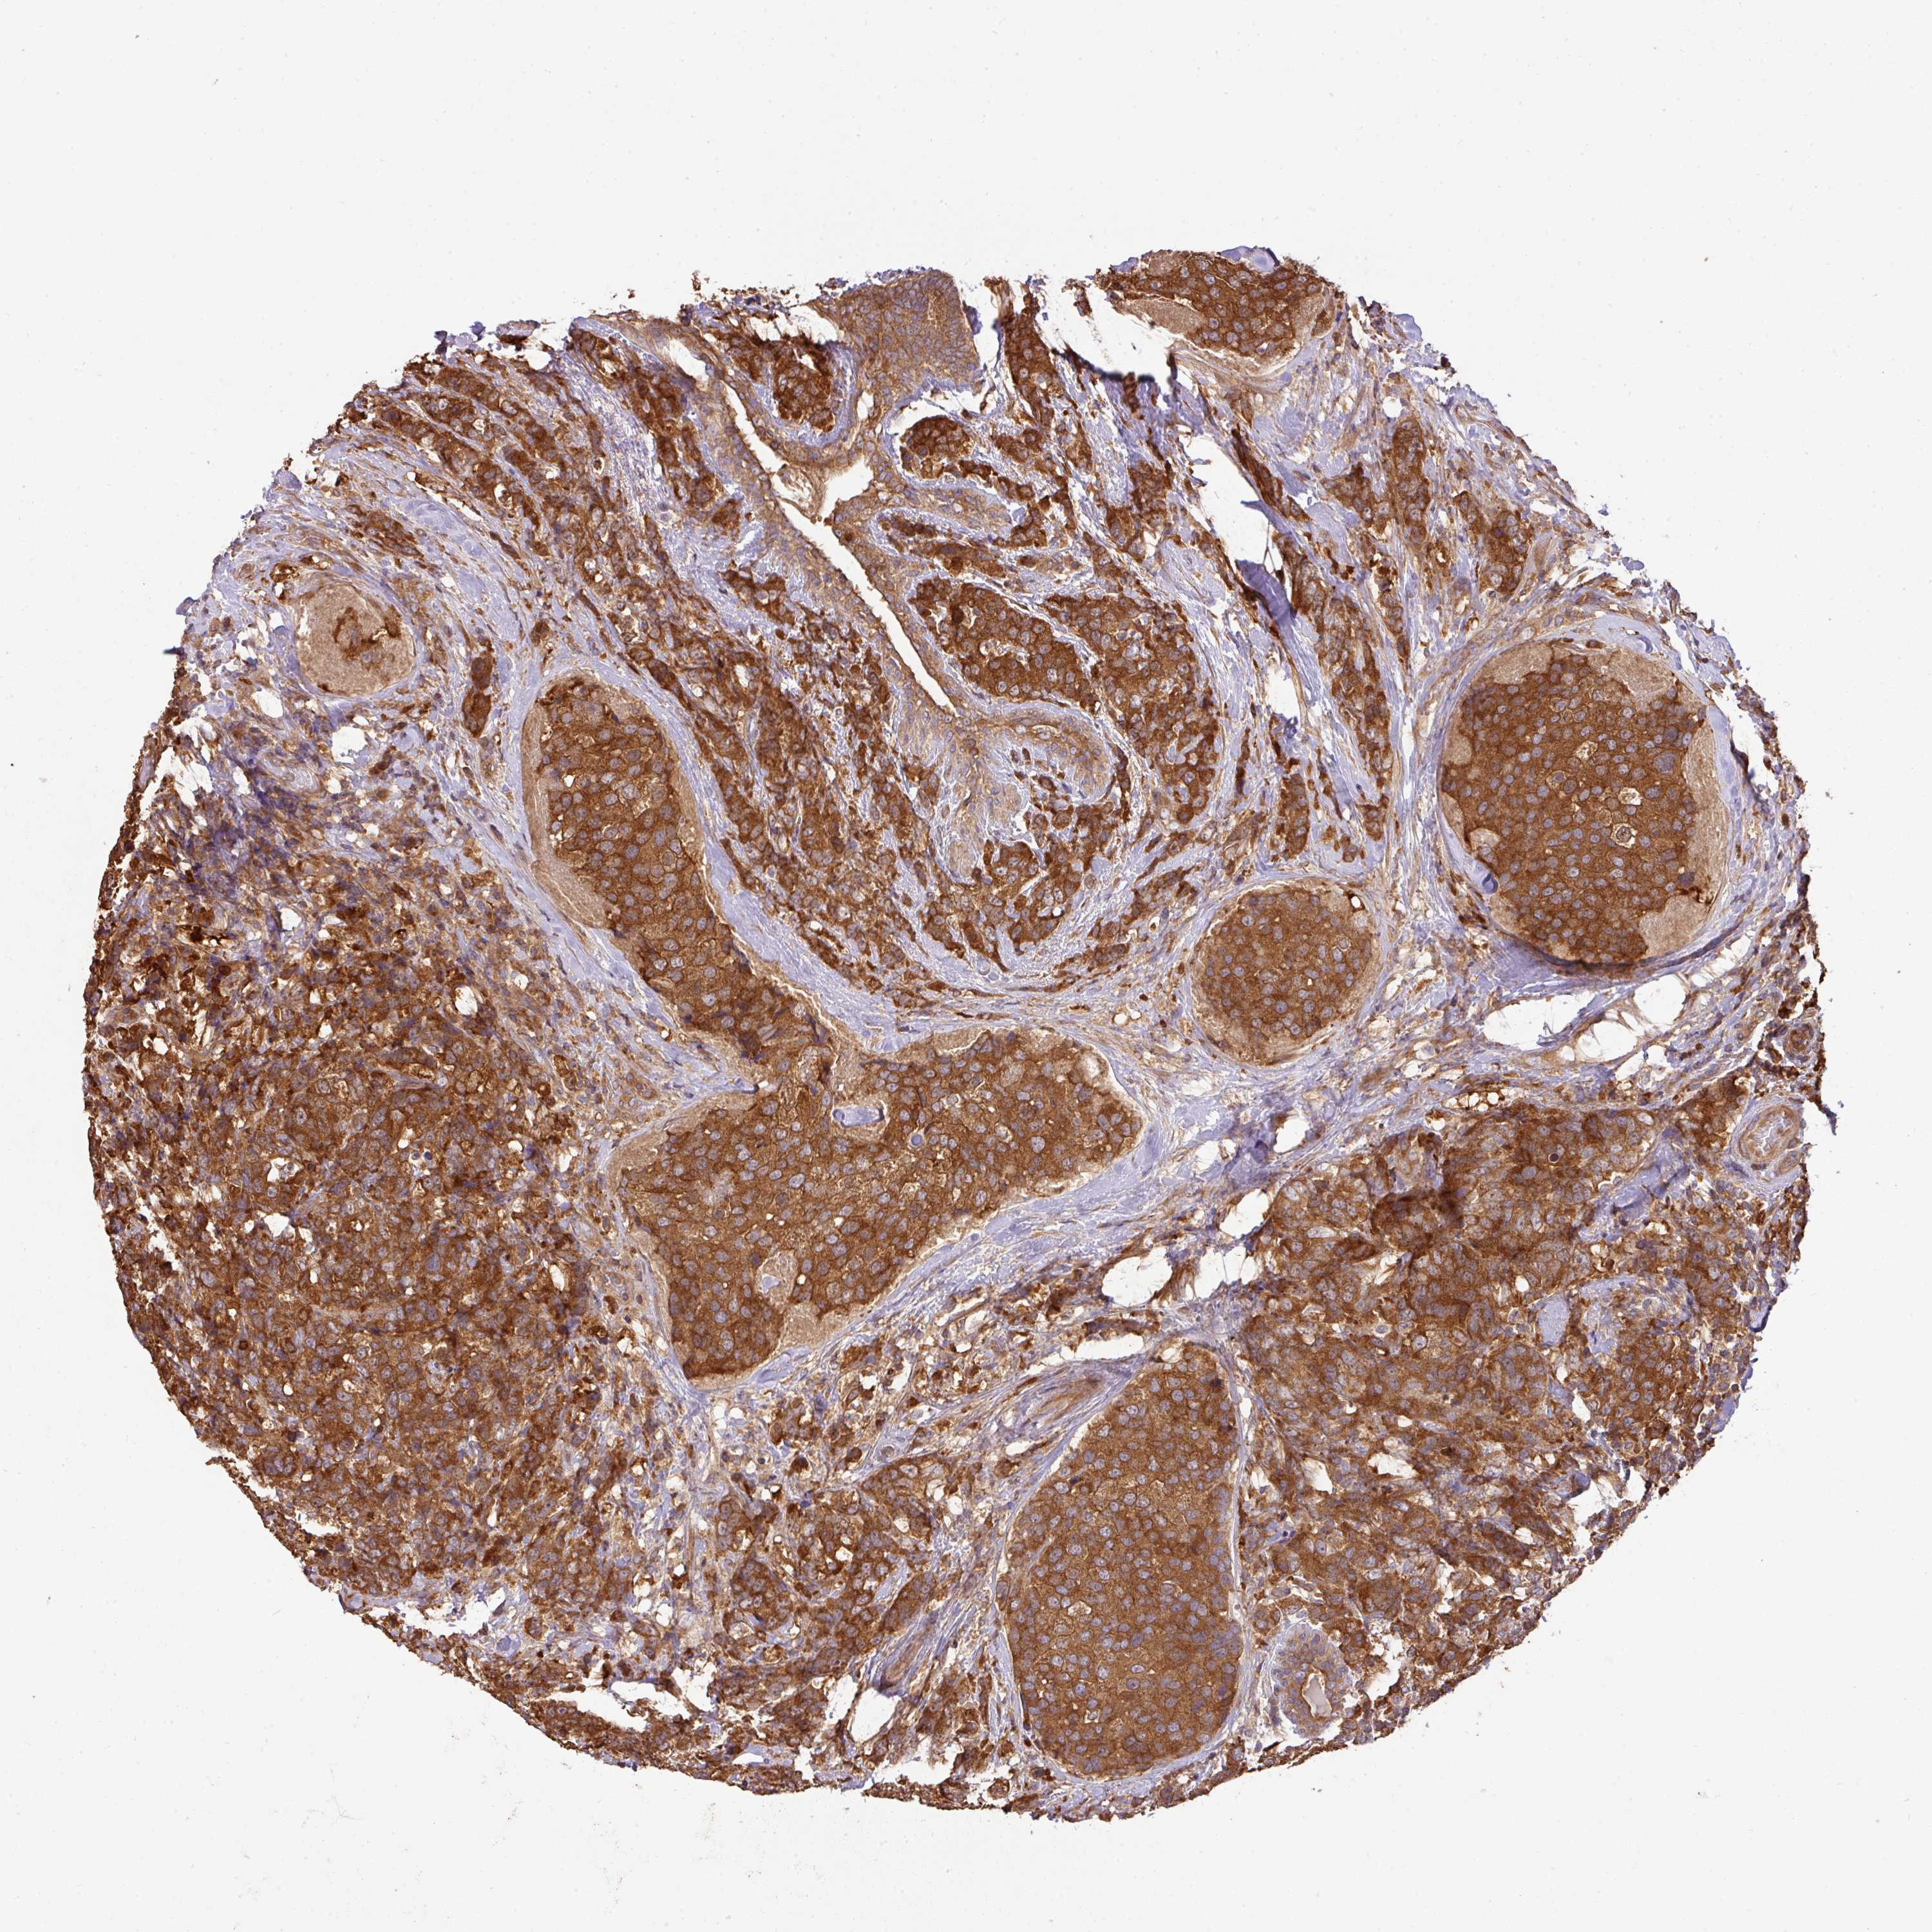

CANCER BREAST CANCER Show tissue menu

BRCA TCGA BRCA VALIDATION PROTEIN EXPRESSION

ANTIBODIES

AND

VALIDATION